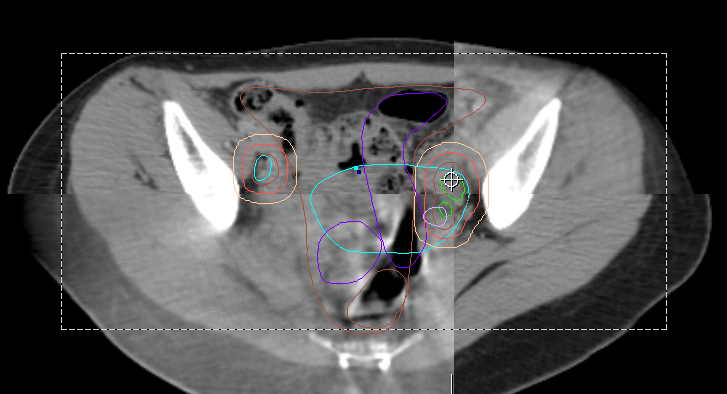

(下方圖片案例:攝護腺癌、婦癌、肺癌、頭頸癌影像導引放射治療,提升放射治療精準度,並且降低鄰近正常器官照射劑量)。

案例二 婦癌癌骨盆影像導引放射治療

案例三 骨盆淋巴結影像導引放射治療